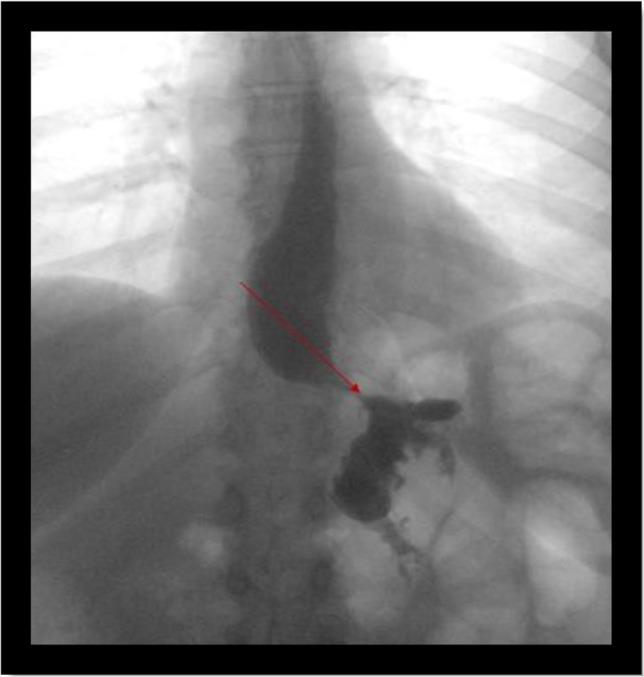

Gastro-gastric fistula is a communication between the gastric remnant and gastric pouch. It is a rare complication of Roux-en-Y gastric bypass. It is caused by anastomotic leak, marginal ulcers, distal obstruction or erosion from foreign body. In this case report, we are presenting a successful laparoscopic repair of gastro-gastric fistula in a patient who presented with weight gain after initial loss.